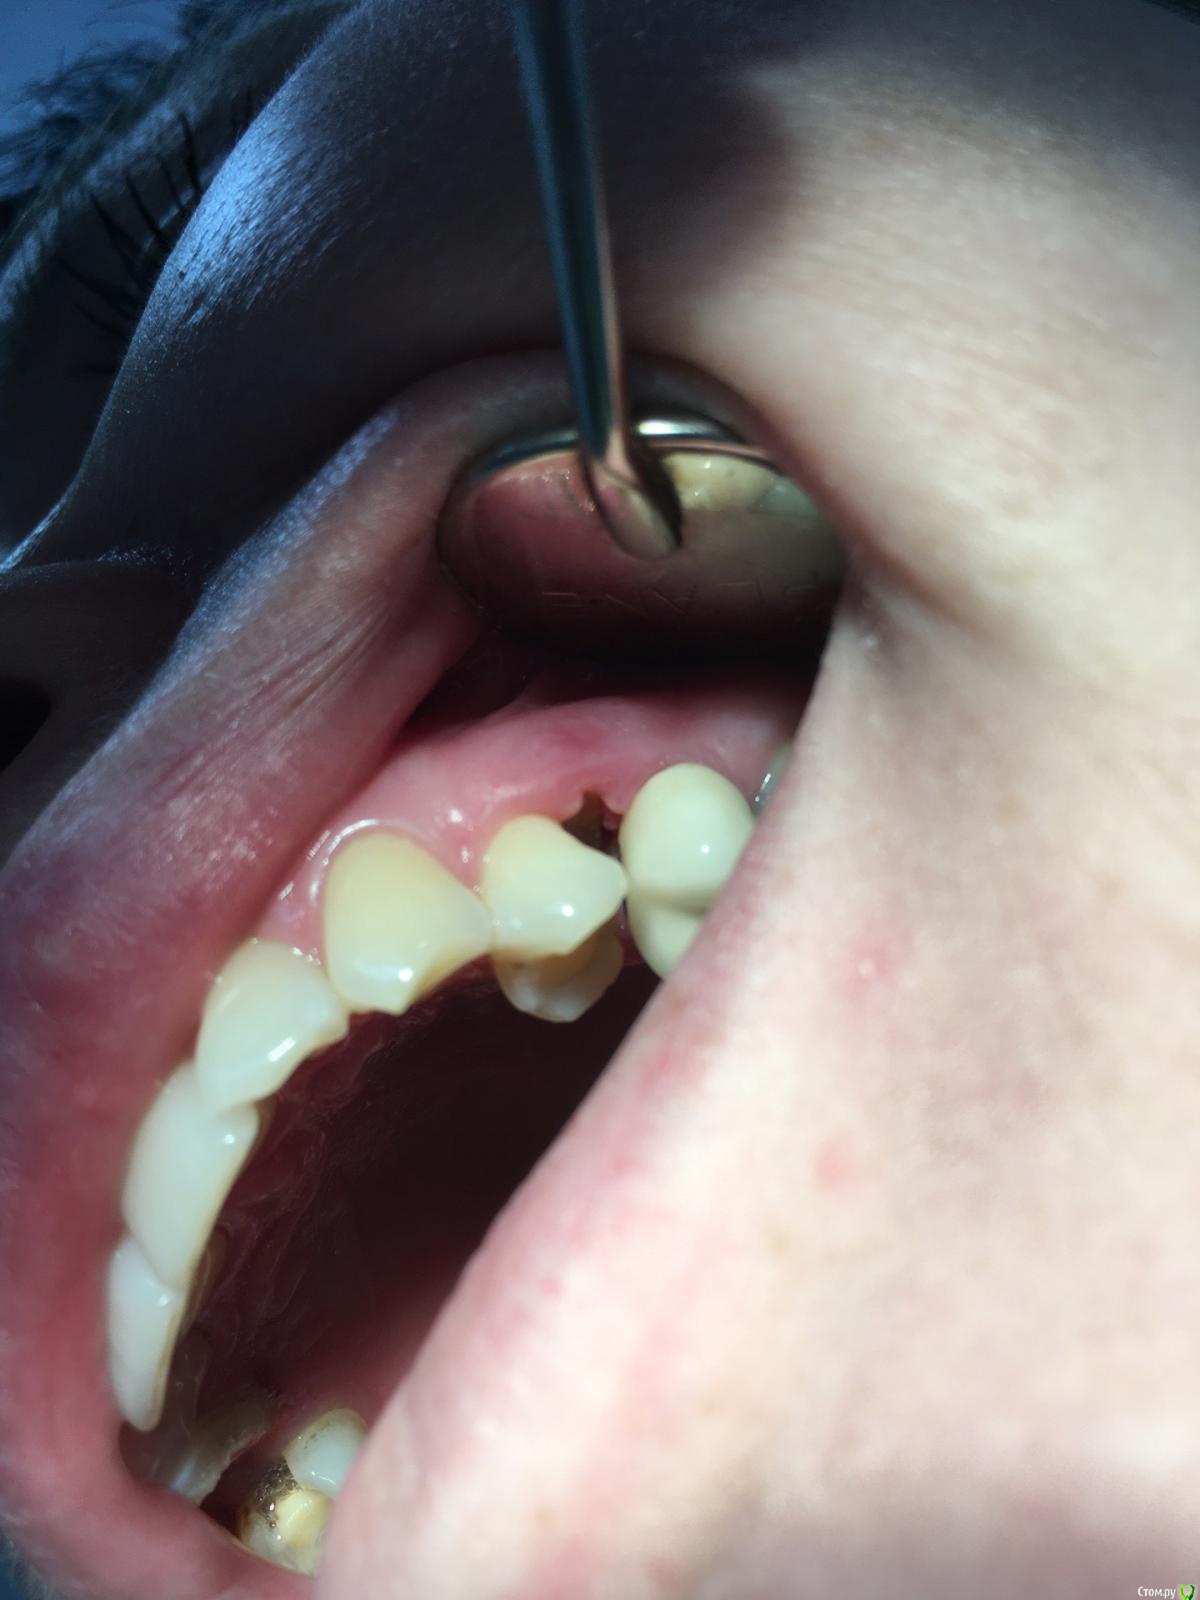

kuziy12 Опубликовано 22 февраля, 2020 Поделиться Опубликовано 22 февраля, 2020 Здравствуйте. Подскажите как лучше поступить. За качество фото извиняюсь, сел акум на основном. Телефон наше все.. Анамнез: 6 месяцев назад поставили мышьяк не очень герметично, неделю пациент ходил, так как не мог записаться. После попал ко мне. Эндо лечение зуба 2.5, удаление распада сосочка, добился крови из кости. Так как пациентка уезжала, постоянная коронка. Объективно:Межзубной сосочек отсутствует, секвестр подвижен, зуб 2.4 и 2.5 - подвижность I степени, перкуссия безболезненна. Сопр без особенностей. Вестибулярная кортикалка между зубами отсутствует. Зуб 2.4 живой. От себя: Если от мышьяка, то почему без острой стадии и как он так интересно подействовал в глубь кости, а не на поверхности? Точно не помню, но вроде в каналах пульпа была живая. Примерная тактика: откинуть лоскут, удалить секвестр, кюретаж. Имеет смысл подсыпать искусственную кость? Ссылка на комментарий

kuziy12 Опубликовано 8 марта, 2020 Автор Поделиться Опубликовано 8 марта, 2020 Как то так. Попытался вообще без откидывания, но тогда бы секвестр десну порвал, большой слишком. Уже его чуть сдвинул:Убрал грануляции:Ушился:Это секвестр: 3 Ссылка на комментарий